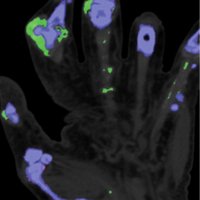

Although diagnosing gout generally is straightforward, atypical disease may present a challenge if it is associated with unusual symptoms or sites, discordant serum urate level, or mimics of gout. Dual-energy computed tomography (CT) may be used to differentiate urate crystals from calcium by using specific attenuation characteristics, which may help diagnose gout. In patients with known tophaceous gout, dual-energy CT may be used for serial volumetric quantification of subclinical tophi to evaluate response to treatment.

Dual-energy CT can quantitatively identify monosodium urate crystal deposits with high sensitivity and specificity within joints, tendons, and periarticular soft tissues.

Given the utility of dual-energy CT in challenging cases and its ability to provide an objective outcomes measure in patients with tophaceous gout, dual-energy CT promises to be a unique and clinically relevant modality in the diagnosis and management of gout.